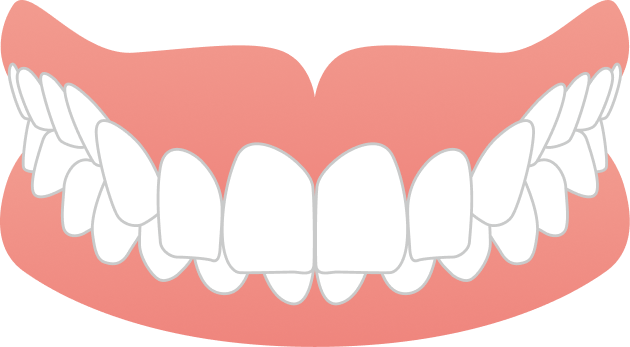

治療では、歯列全体のバランスと噛み合わせを考慮しながら計画を立て、抜歯を行うことなく、マウスピースのみで治療を進めました。治療期間は1年9ヶ月で、見た目の印象が大きく改善するとともに、機能的にも安定した噛み合わせが得られています。

自然な口元と噛みやすさの両立を実現できた症例です。

AFTER